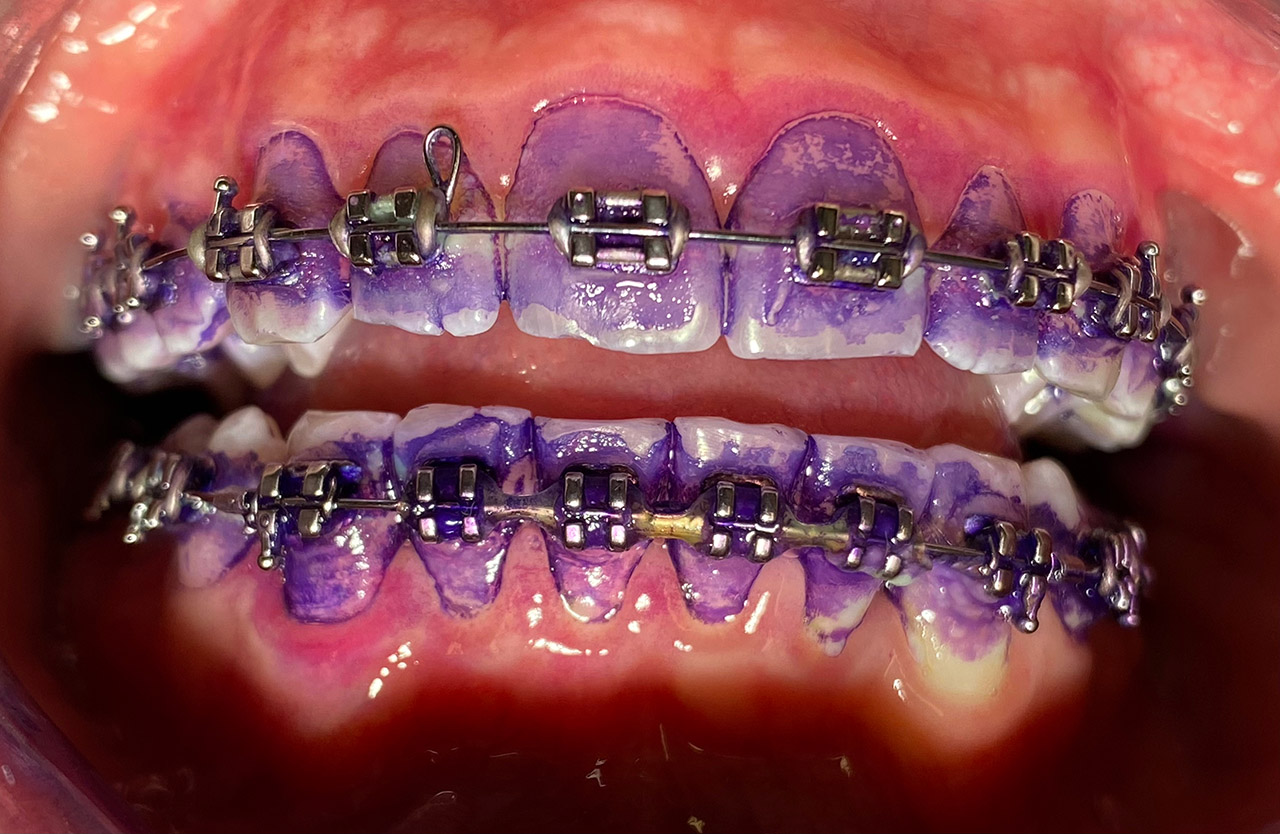

Prophylaxe/professionelle Zahnreinigung:

Zur Motivation, Information und Instruktion einfärben der Beläge (bakterieller Biofilm) bei jungem Patienten in kieferorthopädischer Behandlung. Reinigung der Zähne mit Pulverstrahltechnik minimalinvasiv und zahnschonend und wo noch nötig gezielt mit Ultraschall.

Das Resultat 45 Minuten später.